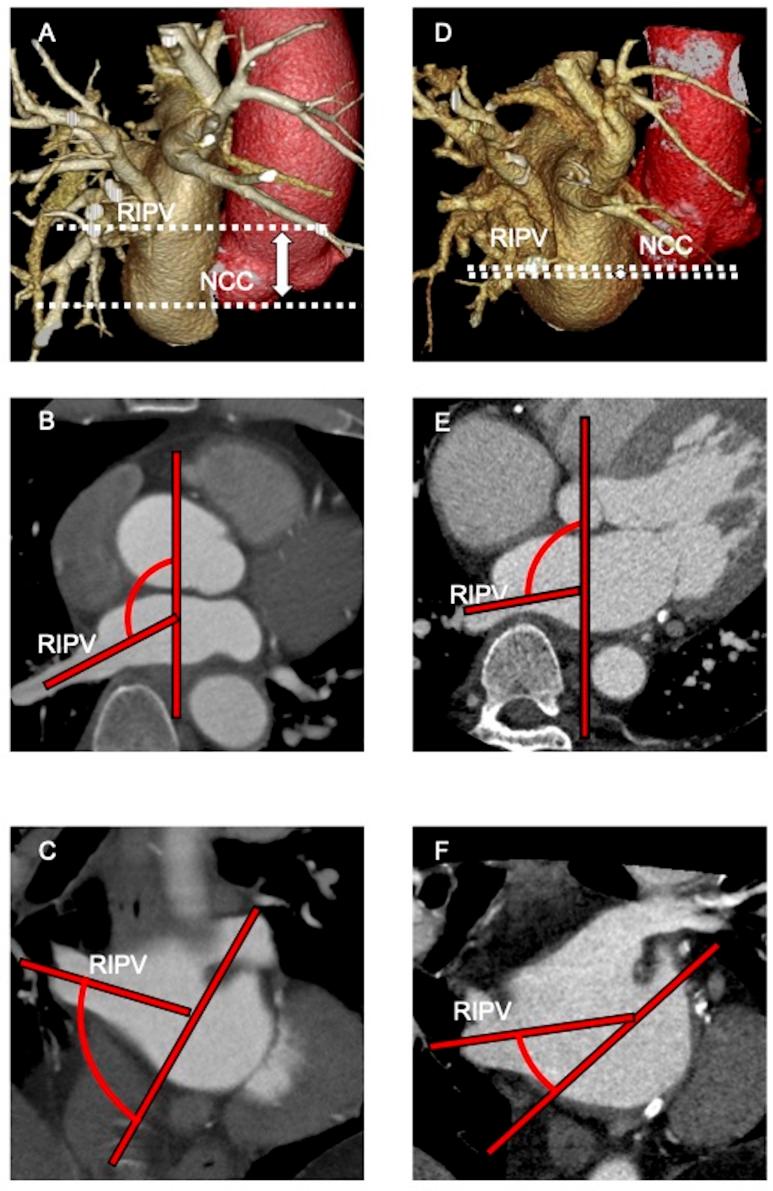

Overall, 243 articles were identified. After screening, 16 articles comprising 1396 patients were included (3, 5 and 8 for acute success, AF recurrence and complications, respectively). Regarding acute success and AF recurrences, thinner width of the left lateral ridge, higher PV ovality, PV ostium-bifurcation distance, shorter distance from the non-coronary cusp to inferior PVs, shallower angle of right PVs against the atrial septum and larger right superior PV (RSPV) were associated with poor outcomes. Regarding complications, shorter distance between the RSPV ostium and the right phrenic nerve, larger RSPV-left atrium angle, larger RSPV area and smaller right carina width were associated with incidences of phrenic nerve injury.

共确定了 243 篇文章。经过筛选,纳入了 16 篇文章,共包括 1396 例患者(分别为 3 篇、5 篇和 8 篇用于急性成功、AF 复发和并发症)。就急性成功和 AF 复发而言,左侧侧嵴较薄、PV 卵圆形较高、PV 口分叉距离较长、从非冠状动脉瓣到下 PV 的距离较短、右 PV 与房间隔的夹角较浅、RSPV 较大与不良结果相关。关于并发症,RSPV 口与右膈神经之间的距离较短、RSPV-左心房角度较大、RSPV 面积较大和右嵴宽度较小与膈神经损伤的发生率相关。